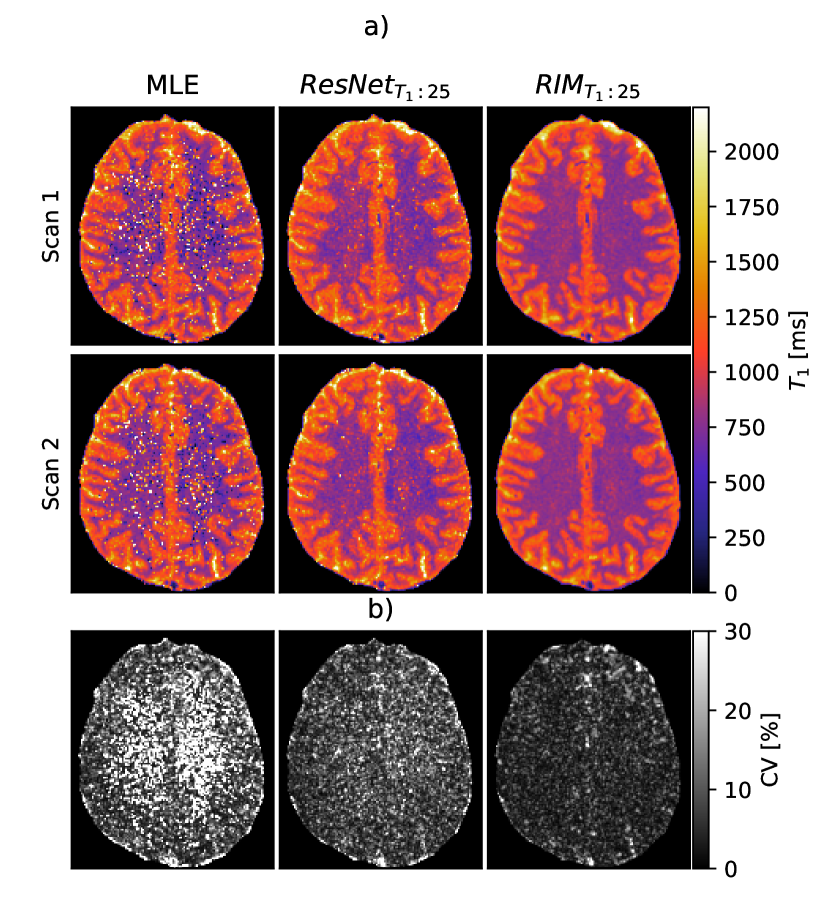

Figure 6: T1subscript𝑇1T_{1} maps estimated from the I​VT1n​o​i​s​y𝐼superscriptsubscript𝑉subscript𝑇1π‘›π‘œπ‘–π‘ π‘¦IV_{T_{1}}^{noisy} dataset a) T1subscript𝑇1T_{1} maps estimated from volunteer 1 for repeated scans 1 and 2. b) Their respective pixel-wise CV map.

T1subscript𝑇1T_{1} maps inferred from the noisier dataset I​VT1noisy𝐼subscriptsuperscript𝑉noisysubscript𝑇1IV^{\text{noisy}}_{T_{1}} are shown in Fig. 6(a). The RIMπ‘»πŸ:πŸπŸ“bold-:subscript𝑻125{}_{\bm{T_{1}:25}} showed increased noise robustness compared to the MLE and ResNetπ‘»πŸ:πŸπŸ“bold-:subscript𝑻125{}_{\bm{T_{1}:25}}, clearly outperforming these methods in terms of outliers. The CV maps, computed per pixel, are presented in Fig. 6(b) and shows that the RIMπ‘»πŸ:πŸπŸ“bold-:subscript𝑻125{}_{\bm{T_{1}:25}} model produces low-variance quantitative maps, with average CV over all pixels equal to 6.4%percent6.46.4\%, compared to 17.1%percent17.117.1\% from the MLE and 11.06%percent11.0611.06\% from the ResNetπ‘»πŸ:πŸπŸ“bold-:subscript𝑻125{}_{\bm{T_{1}:25}}.

To evaluate the precision of estimates from in-vivo data, we compared T1subscript𝑇1T_{1} and T2subscript𝑇2T_{2} maps from all methods in terms of pixel-wise CV for all in-vivo scans. We also performed a visual comparison of the maps.